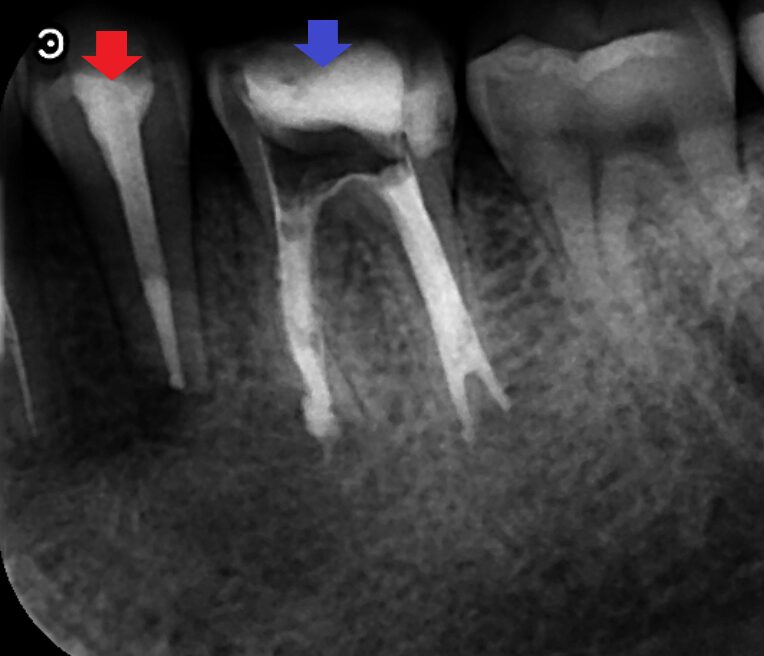

下顎第二小臼歯と下顎第一大臼歯の矢状断のCT画像です。

赤い矢印の先は下顎第二小臼歯と下顎第一大臼歯の近心根の両方の根にまたがる膿の影です。根の先が平で、外科手術により根の先を切断したようにみえます。青い矢印の先に下顎第一大臼歯の遠心根にできた膿の影がみられますが、こちらは切断されているようには見えませんでした。